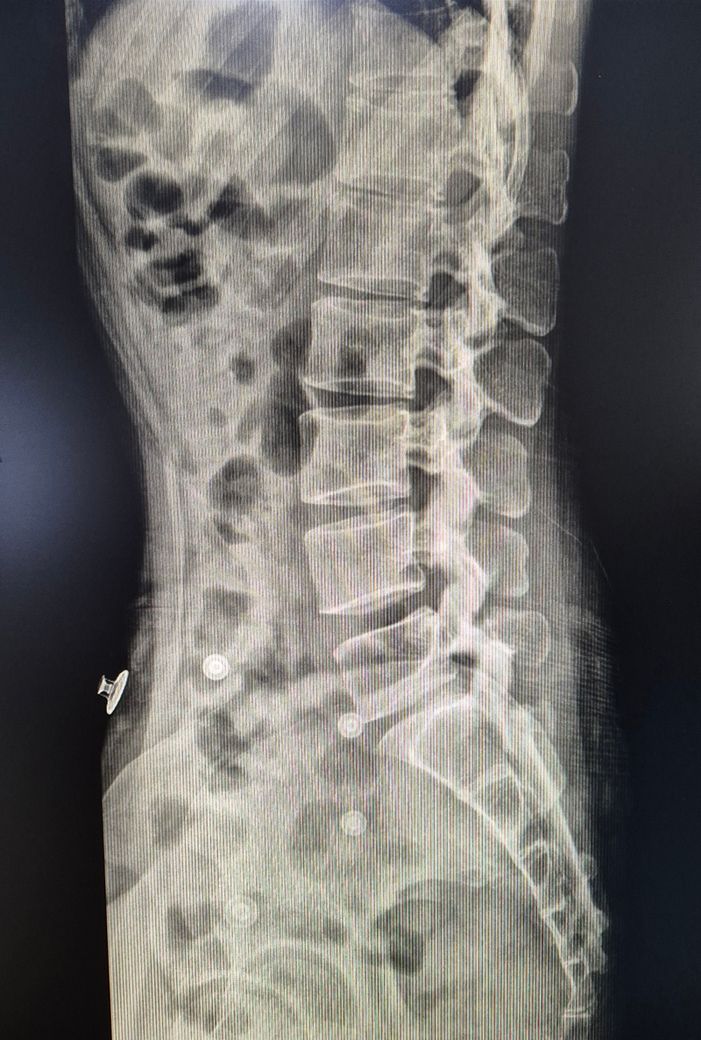

허리 디스크 심한 편인가요? (사진有)

허리에 시큰거리는 통증이 생겨서 병원 갔더니 엑스레이 찍더라구요

요추5번 천추1번 사이(?)라고 들은 것 같은데;

암튼 꼬리뼈로 이어지는 디스크가 좁아진 거라며 디스크라는데

엑스레이상에서는 디스크를 판단할 수 없습니다. 예측은 할 수 있습니다. 엑스레이상 볼때는

등이랑 허리 부분이 뻣뻣할것으로 보이며 (만곡이 거의 없이 일자 허리로 되어 있는 것으로 유추)

허리뼈 5번이랑 꼬리뼈 1번 척추 간격이 상당히 좁습니다. 간격이 좁게 되면 허리가 뒤로 재끼거나

질문자분의 엑스레이 사진을 보았을때 일단 허리뼈 5번이랑 꼬리뼈 1번 척추뼈 사이 공간이 조금 좁기는 하지만 정확한 상태를 확인하고 싶으시다면 역시 MRI를 찍어보시는게 좋을것 같습니다.

요추5번과 천추1번사이가 많이 좁아져있습니다. 좁아져있는 경우는 단순히 좁은것뿐만아니라 오랜기간에 허리긴장도가 높은상태로 유지되어있었기때문에 그부분도 상당히 중요합니다. 허리를 숙이거나 뒤로꺾는동작은 현재 근육상태가 좋지않을가능성이 높기때문에 오히려 관절에 무리를 줄수있습니다. 디스크가 어느방향으로 얼마나 나와있는지는 mri를 찍어야 더 정확하게 알수있으나 공간이 좁아진것으로봐서 디스크는 확실히있습니다. 다만 이 디스크가 뒤로빠진것인지 옆으로빠진것인지 좌측인지 우측인지를 알기위해 mri가필요한것입니다. 일단 비수술적으로 접근한다면 꾸준한 코어운동이 필요합니다. 코어운동으로 허리의 근육을 잘컨트롤할수있을때는 굽히거나 숙이는동작도 허리에 무리없이 하는경우가 많습니다. 하지만 지금은 최대한 안하시는게 맞습니다. 고로 재활전문가와 함께 코어운동을 꾸준히 하시는것이 좋고 그 전에 먼저 시술이나 수술이 필요한경우인지 아닌지 mri를 찍어보시는것이 우선입니다. 수술이나 시술을 하지않고 재활만으로 가능한 단계인지 시술 수술을하고나서 재활운동을 해야하는단계인지를 먼저 상태를 보셔야합니다.